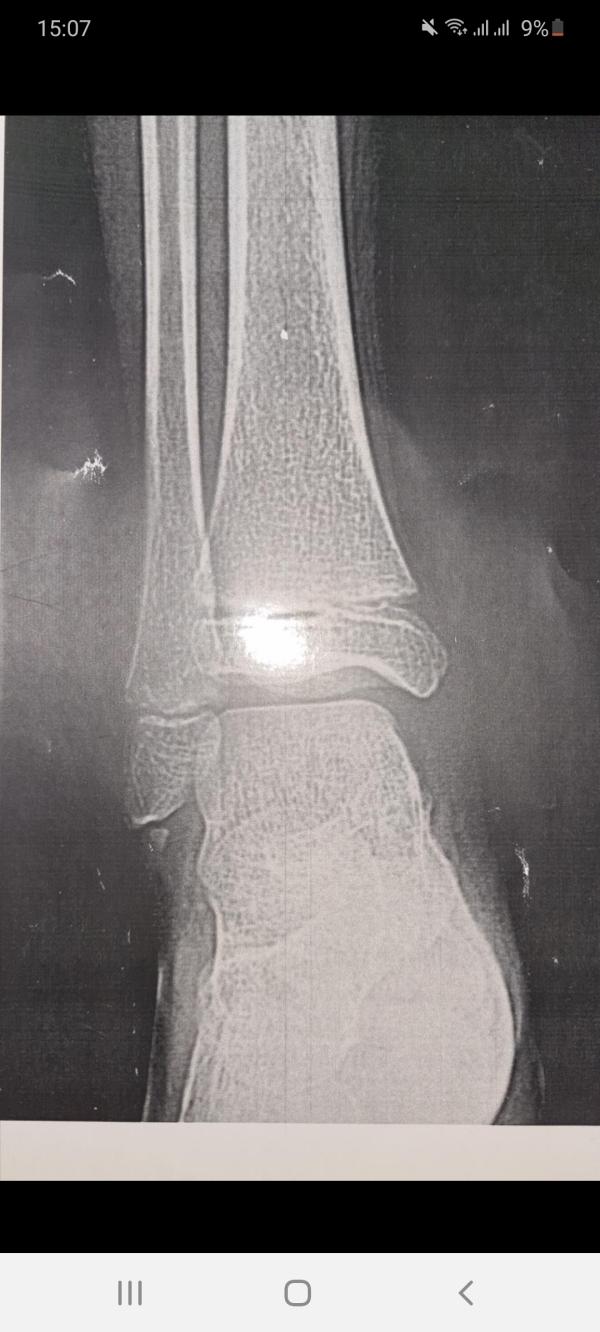

Привет девочки! Посоветуйте к какому врачу идти, травматологу или ортопеду?

У сына отрыв костного фрагмента наружной лодыжки.

Сыну 10 лет, есть ли в кокшетау детские врачи ортопед либо травматолог? Заранее спасибо всем участвующим!😘